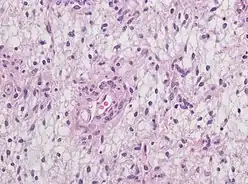

Histopathology specimen of Angiocentric glioma, higher magnification, HE stain

Neuropathology is a specialty within the study of pathology focused on the disease of the brain, spinal cord, and neural tissue.[33] This includes the central nervous system and the peripheral nervous system. Tissue analysis comes from either surgical biopsies or post mortem autopsies. Common tissue samples include muscle fibers and nervous tissue. Common applications of neuropathology include studying samples of tissue in patients who have Parkinson's disease, Alzheimer's disease, dementia, Huntington's disease, amyotrophic lateral sclerosis, mitochondria disease, and any disorder that has neural deterioration in the brain or spinal cord.[34][35]